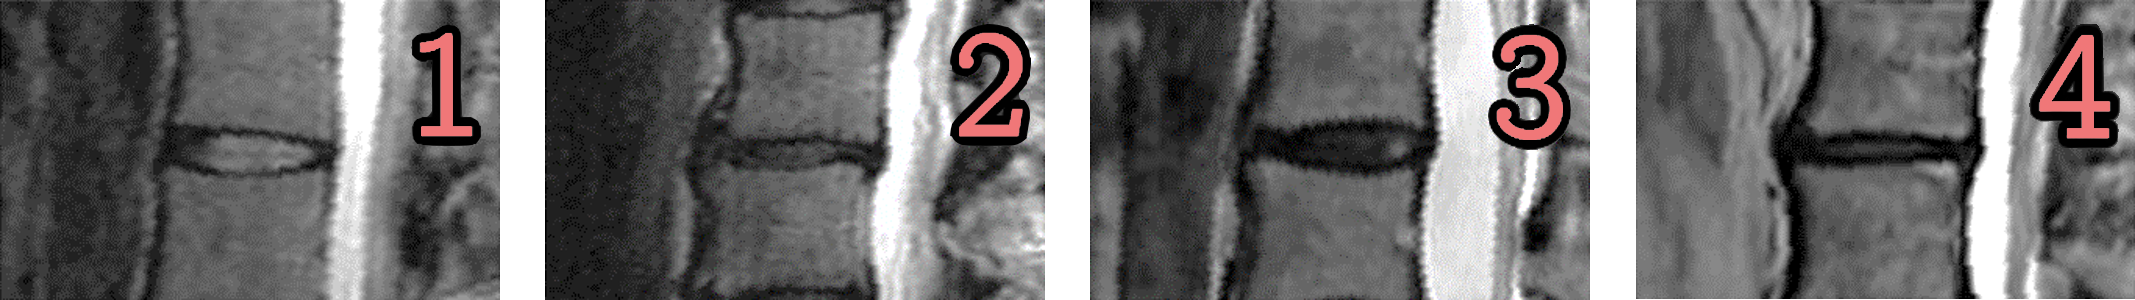

The subjects were graded with a measure of Disc Degeneration, not dissimilar to Pfirrmann Grading. The gradings were annotated by a clinician and were done on a per disc basis: from L1-L2 to L5-S1 discs (5 discs per subject). We use these gradings to assess the benefits of pre-training a classification network on longitudinal information. Examples of the gradings can be seen in Fig. 5. 920 of the 1016 subjects are graded.

Refer to caption

Figure 5: Disc Degeneration: A four-class grading system based on Pfirrmann grading that depends on the intensity and height of the disc.